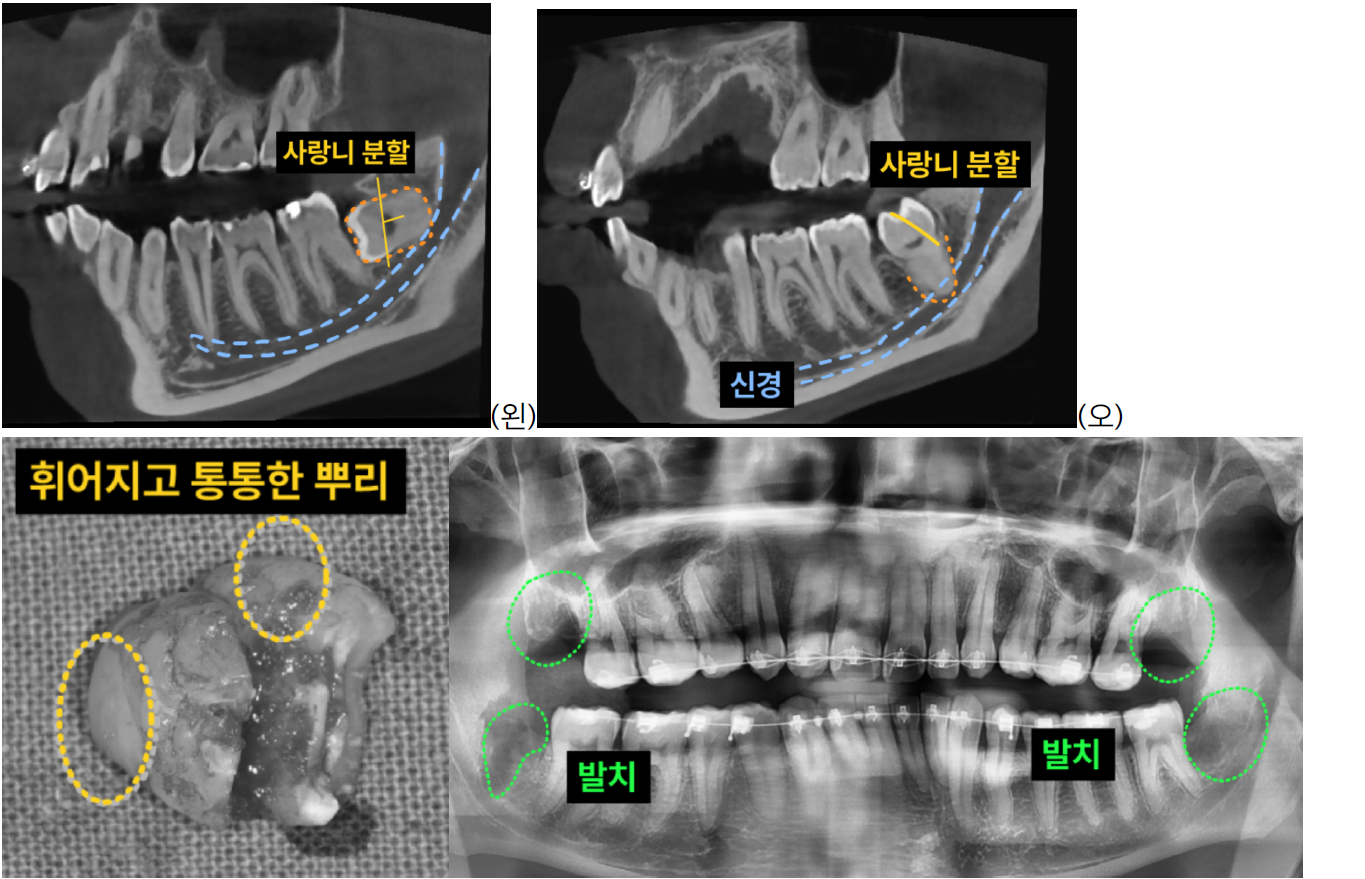

- 3D CT 촬영을 통해 사랑니의 정확한 위치와 매복 정도, 그리고 주변 신경관과의 관계를 면밀히 분석했습니다.

- 왼쪽 아래 사랑니는 가로로 깊이 매복되어 신경과 매우 가까웠으며,

- 오른쪽 아래 사랑니는 신경과 근접한 것은 물론 뿌리가 크고 통통하며 'ㄱ'자 형태로 휘어진 고난이도 형태였습

니다.

2. 정밀 분할 발치: 특히 깊이 매복되어 신경과 가까운 사랑니는 신경 손상 위험을 최소화하기 위해

사랑니의 머리(치관)와 뿌리(치근)를 적절히 분할하여 조심스럽게 발치합니다. 이 과정은 숙련된 의료진의 정교한 기술이 필수적입니다.